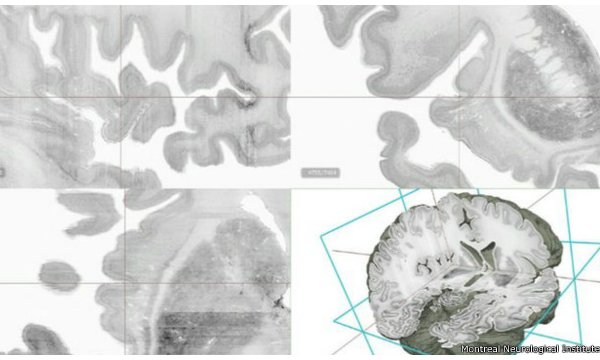

La reconstrucción muestra la anatomía del cerebro a un detalle microscópico.

La reconstrucción muestra la anatomía del cerebro a un detalle microscópico, que le permite a los académicos ver características minúsculas.

Para su creación el equipo de académicos cortó 7.400 secciones en el cerebro de una mujer de 65 años de edad.

Cada una de esas capas tenía la mitad del grosor de un pelo.

Después, tiñeron cada sección para hacer resaltar cada detalle anatómico e hicieron escáneres de alta definición para pasar la información a una computadora.

El paso final fue recomponer digitalmente todas las capas escaneadas.

En total, se capturaron 80.000 millones de neuronas en un minucioso proceso que tomó 10 años.

El resultado es un cerebro digital de alta definición y en 3D en el que los investigadores pueden sumergirse para estudiar áreas de interés con un detalle microscópico.